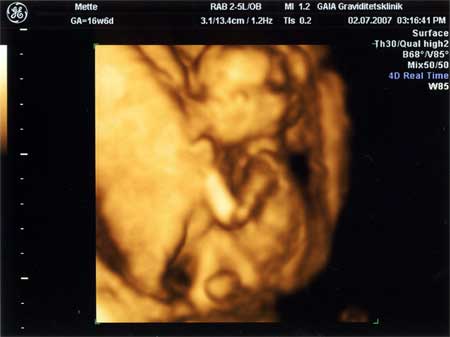

3D scanning – se baby i maven under graviditeten

3d scanning uge 16

3d scanning – uge 16

uge 16+3

En dreng :O) tappen ses meget tydeligt